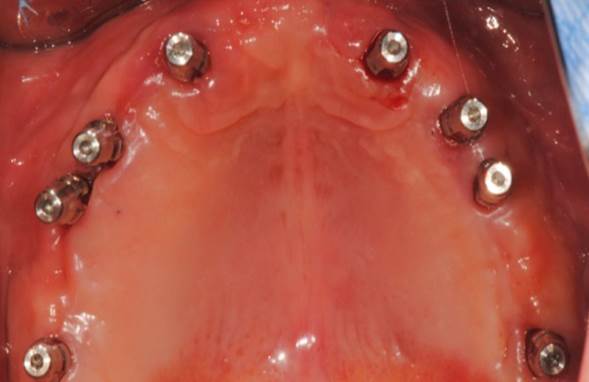

“AnyRidge shows excellent initial stability

& stable results after immediate loading in

upper fully edentulous case. ”

Clinical case: Extraction of all teeth in upper maxilla,

immediate implant placement, & provisionalization

- Courtesy of Dr. Iulian Filipov, Romania -